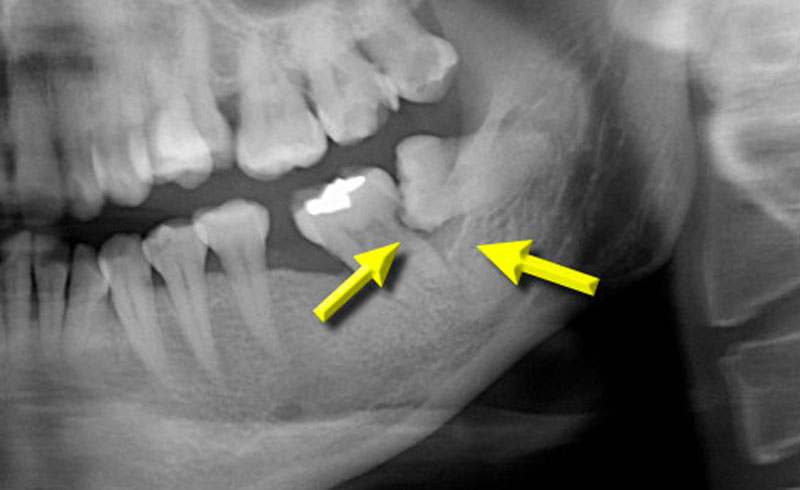

智齒不只造成牙周病,同一顆智齒也造成鄰接的第二大臼齒蛀牙,箭頭指的黑色部分就是被蛀空的牙齒。

左下顎水平智齒造成前面的第二大臼齒牙根蛀牙和牙周病,前面的第二大臼齒牙根蛀牙往往沒辦法填補,嚴重的需要拔牙。